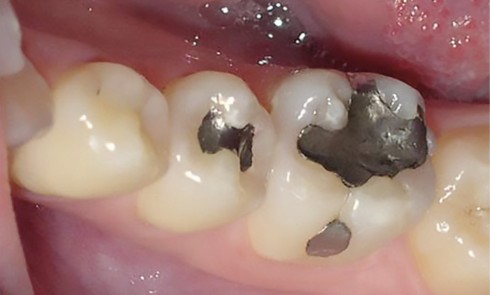

Article réservé à nos abonnés Amélogenèse imparfaite et maladie rare : réhabilitation par prothèses amovibles

L’amélogenèse imparfaite (AI) est un groupe de maladies héréditaires hétérogènes sur le plan génétique et phénotypique qui affecte la qualité...